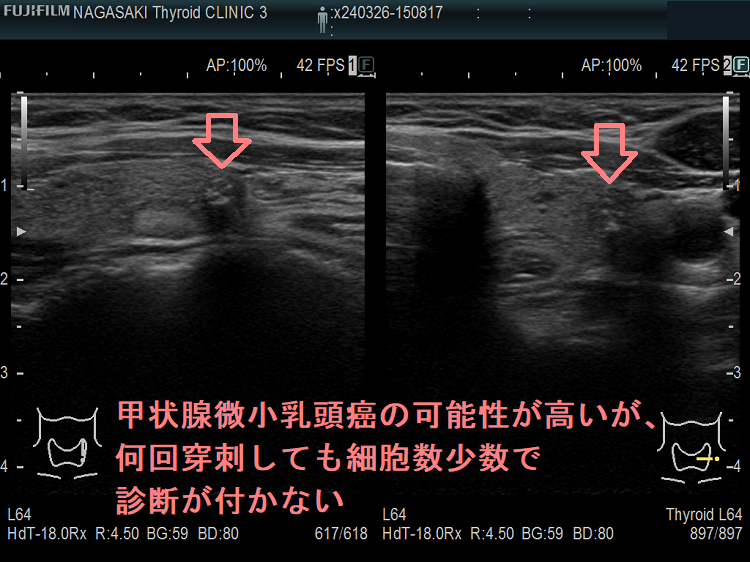

ケース⑤ 甲状腺微小乳頭癌 僅かに前方被膜浸潤

何回穿刺しても細胞数少数で診断が付かない